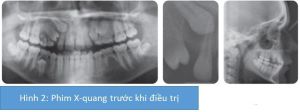

Nhận xét về phim X-quang

Phim Xquang cho thấy R13 mọc ngầm phía khẩu cái với tiên lượng làm đều thuận lợi bằng chỉnh nha. Có sự mở rộng bao răng của răng này nhưng không có tiêu chân R12. R25, R15 và R35 thiếu bẩm sinh. Tất cả các răng hàm lớn thứ 3 đang phát triển.